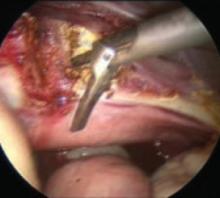

FIGURE 5 Supracervical hysterectomy

Begin the procedure at tissue level 1 using reverse cone drilling to reach the level 2 endpoint.